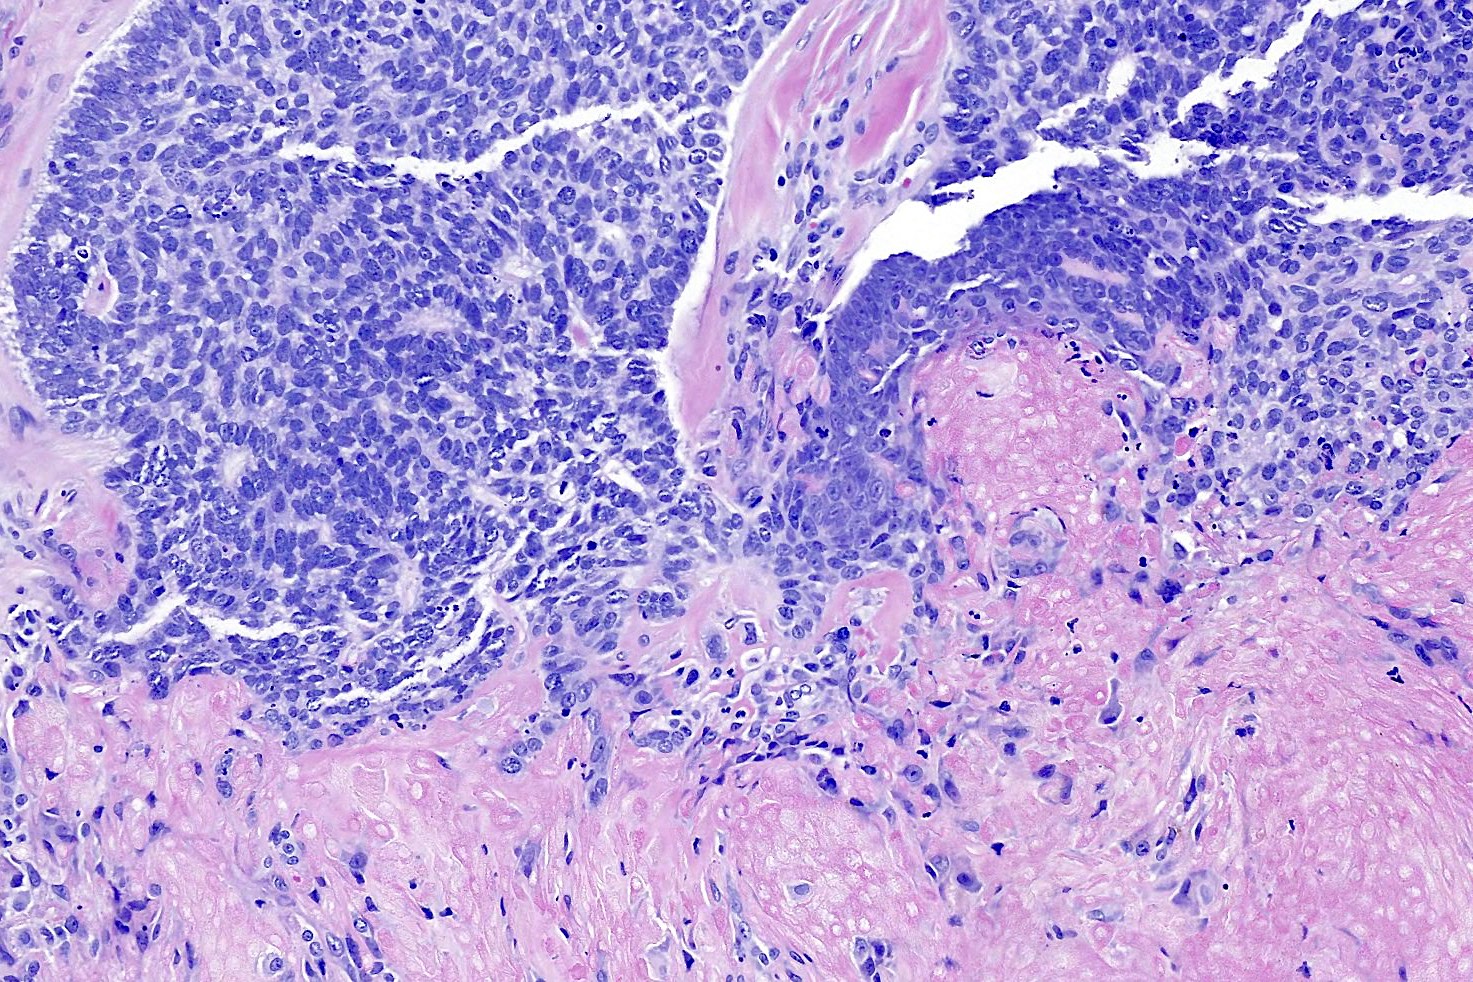

Common variants (Calonje: McKee's Pathology of the Skin, 5th Edition, 2019)

- Basosquamous (metatypical) BCC

- Biphasic tumor

- Foci of neoplastic squamous differentiation

Microscopic (histologic) images

Contributed by Antonina Kalmykova, M.D., Phillip H. McKee, M.D., Sate Hamza, M.D., Eduardo Calonje, M.D.,

Wayne Grayson, M.B.Ch.B., Ph.D., James Sampson, M.B.B.S., M.Sc. and Assia Bassarova, M.D., Ph.D.

- Squamous cell carcinoma (basaloid, clear cell, sarcomatoid):

- Shows an intraepidermal component, pagetoid spread

- No peripheral palisading, clefting or myxoinflammatory stroma

- Areas with conventional features like keratinization, keratin pearls

- BerEP4- (also absent in squamous areas of basosquamous carcinoma)